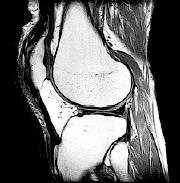

RESONANCIA MAGNÉTICA. Se trata de una prueba detallada de diagnóstico por imágenes en la que se pueden observar los huesos, cartílagos, ligamentos y otros problemas musculares sin usar rayos X.